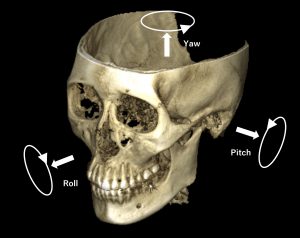

矯正診療によるCBCT(3D)、口腔内3Dスキャンはイタリアで製造され2001年から世界に投入されていきました。

口腔、顎顔面複合体に関する診断は2次元(2D)だけでは正確な診断情報を得ることが難しかったですが、CBCTを活用することにより複雑な解剖学的構造と関連する病状を明らかにすることができるようになりました。

私達矯正歯科医はCBCTを使用することで子供の成長する顎の発育など観察することができるようになり、矯正を必要とする子供の顎は早期に矯正しないと変形に繋がっていくのでその診断をするのにとても有効です。

またCBCTを使用して咬合機能を回復させる診断にも役に立ち、歯を直立させるための診断も精密に出せるようになりました。せきど矯正歯科もCBCTを使用しています。